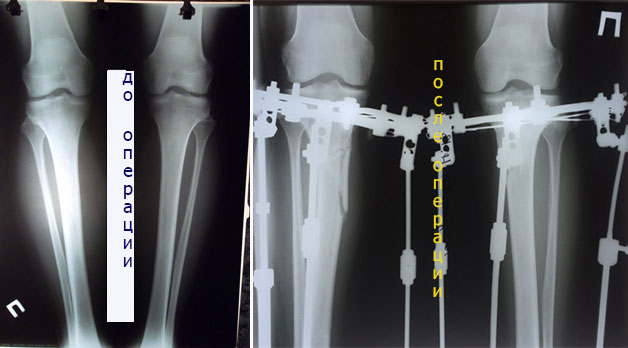

Re: Iskorka ☻

ножки в аппаратах, в день снятия.